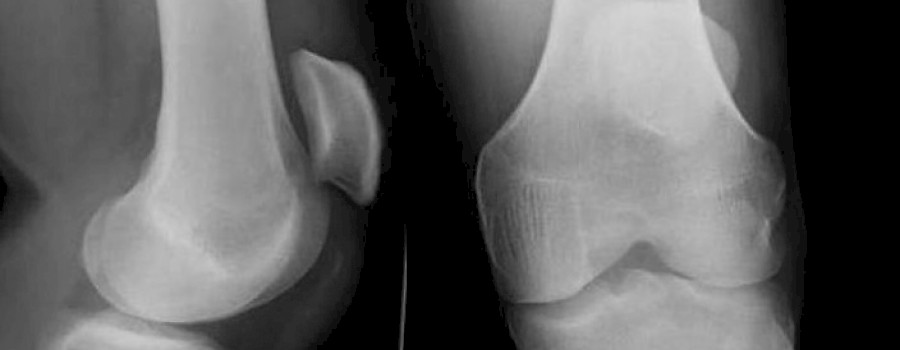

Die Patellarsehnenruptur ist ein Riss der Sehne zwischen dem unteren Pol der Kniescheibe (Patella) und dem Schienbeinhöcker (Tuberositas tibiae).